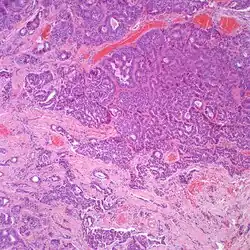

At the time of surgery, the tumor tends to peel away from the adjacent bones, although not the ossicles. It is usually fragmented, soft, rubbery and white to gray-tan. Due to the anatomic confines of the region, tumors are usually <1 cm.[8] The tumors arise below the surface, are unencapsulated, and have an infiltrative pattern of growth, composed of many different patterns (glandular, trabecular, cords, festoons, single cells). The tumor shows duct-like structures with inner luminal, flattened cells and outer, basal, cuboidal cells. The cells may have an eccentrically placed nucleus. The nuclear chromatin distribution is "salt-and-pepper", giving a delicate, fine appearance. Nucleoli are small with inconspicuous mitoses. There may be secretions in the gland tumor. It is possible to see a concurrent cholesteatoma.[2]